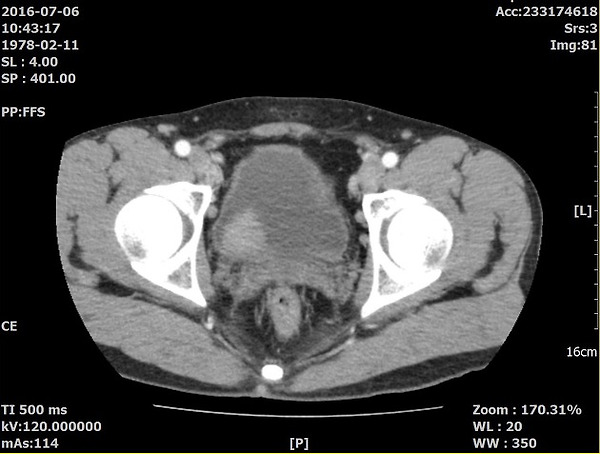

남편이 얼마전 2016년 7월에 혈뇨와 함께 결박뇨, 빈뇨로 인하여 부산 남구 S병원에 내원하여 ct를 찍었는데 방광에 4센티 가량의 혹이 보인다고 수술을 해야한다고 하는 것입니다. 급히 부산대학병원에 의뢰를 해서 수술일정을 잡기위해  내시경을 하니 조직검사는 해봐야겠지만 암으로 보인다고...수술을 해야될 것같다는 것입니다.

혈뇨가 이번이 처음은 아닙니다. 2011년 4월에도 혈뇨로 부산 s병원에서 ct를  찍었는데 이상없음. 그 후로 증상이 없다가 2015년 1월에 또 혈뇨로 동병원에서 ct찍으니 또 이상소견없음...

제가 좀....공부랑은 거리가 멀지만 이상하게 하나하나 해석하고 싶드라구요. 오른쪽 간에 작은 물혹의심병변이 있음..여기에 꽂혀서 아는 의사에게 소견서를 찍어서 보냈습니다. 그 의사분이...그건 별로 중요하진 않고 다른게 이상한데...Urothelial tumor 소견에 2011/4/22 ct상에서는 focal nodular enhancing lesion으로 보였던것으로 추정함. 이라고 객관적 소견에 나와있는데....이부분이 이상하다고

분명 그동안 CT소견 이상없음 아니냐고 삼성병원에서의 소견은 2011년도 CT에 항진병변이 보였다는건데 이거 못보고 놓친것 같다고. 본인이 CT를 한번 봤으면 좋겠다고 하데요.

그 의사가 CT를 보더니 조형제를 넣었을때 사진에서 혹으로 의심할만한 모양이 보인다고...2011년 CT에서 2015년 CT는 말할것도 없고....오진인것 같다고...초진병원에서 CT판독을 잘못한거였습니다.....

방광암진단을 받았는데 서울삼성병원에서 이번에 찍은 ct가 아니라 5년전에 찍은 2011년 ct에서 종양 소견이 보인다고 하네요...이게 사실이라면 초진병원을 그냥 넘어가진 않을려구요...

위사진은 암으로 추측되는부분이라도 개인병원 의사가 찾아주신 자료 중 하나입니다.

이게 맞을까요? 첫번째  2011년, 그다음 2015년 세번째도 2011년 그다음 2016년입니다. ....

올려주신 영상은 PELVIS 쪽의 조영증강(ENHANCED) CT 검사네요.

첫째, 셋째 사진이 2011(초진검사) 하신 영상이고,

둘째 ,넷째 사진이 15,16년 사진이시죠.

사진이 명확치 않아 확인지 조금 어렵지만

사진상에 보이는 것은 네번째 마지막 사진에만 확실한 종양의심부분이 관찰이 되고 있습니다.

첫번째 사진 2011년 4월22일 ENHANCE CT 영상에서도

동그라미 쳐진 부분(화살표) 부분이 조영증강된 것이 확인이 됩니다.

나머지도 보시기 쉽게 동그라미 표시를 해드렸습니다.